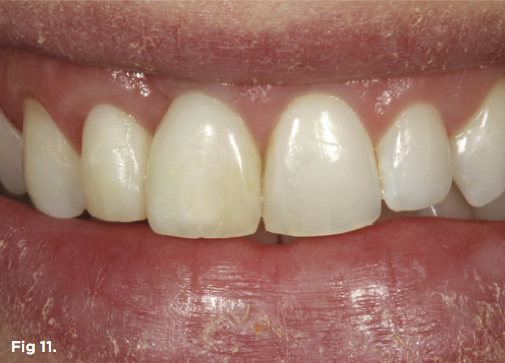

Fig 11. The smile of the patient in provisional restorations tooth No. 7 and implant No. 8 after correction and healing of the periodontium.

Figure 11

After 6 months of healing of the implant, stage 2 uncovering was performed and the mucosal tissues were allowed to mature for another 2 to 3 weeks. A temporary screw-retained implant cylinder was joined to the implant and acrylic crown (Figure 8). The subgingival shape of the temporary was modified with additional acrylic and the technique of non-surgical tissue sculpting, which was developed to provide the proper emergence profile to the mucosal tissues.27 It is important that the temporary blanching (ischemia) of the mucosal tissues dissipate after 10 minutes (Figure 9). After 3 weeks, soft-tissue scalloping through gingivectomy was done to recreate the proper shape (ie, gingival zenith)28 and proportion for the mucosal tissues (Figure 10). Fiberotomy on the distal aspect of tooth No. 7 was not performed during treatment; therefore, this papilla was slightly more incisal (longer) than the adjacent papillae (Figure 11). A final impression was made of crown No. 7 and implant No. 8 at the implant level to enable a working cast to be made in the laboratory. An all-ceramic custom abutment was made for implant No. 8, and splinted full-coverage units were made for crowns No. 7 and No. 829 (Figure 12). The custom abutment was seated intraorally and torqued according to the manufacturer’s recommendation. The crowns were luted with provisional cement and maintained at 4-month recall intervals (Figure 13). Note the health of the periodontal tissues and its integration with the adjacent teeth and surrounding gingiva, taking a complex esthetic and functional problem for a patient with a high smile line and providing a predictable restorative and esthetic outcome (Figure 14).